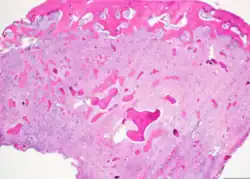

Cemento-ossifying fibroma is a well-demarcated lesion, often encapsulated by a thin fibrous capsule and sharply separated from adjacent normal bone. It shows significant internal variation, with differing amounts of fibrous and mineralized tissue—even within the same lesion. Mineralization is often more prominent centrally and typically includes osteoid, woven to lamellar bone, and dense basophilic cementum-like calcifications. Bony trabeculae may fuse into broad sheets or form thick, anastomosing strands. Osteoblastic rimming is commonly seen around bone trabeculae.[27]

The stroma is fibroblastic and may exhibit areas of hypercellularity and nuclear hyperchromasia; however, mitotic activity is rare and cellular atypia is minimal .[28] The mineralized component may include acellular or paucicellular cementum-like spheres along with bone structures .[28]

Though rare, hemorrhagic cystic degeneration—resembling aneurysmal bone cyst formation—can occur, more commonly in juvenile variants.[27][29] Histological overlap can exist among subtypes: psammomatoid and trabecular JOF may exhibit features resembling COF, and vice versa. In syndromic cases, such as gnathodiaphyseal dysplasia, COF lesions appear more fibrous with basophilic, acellular bone droplets and spherical ossicles, but histologically resemble nonsyndromic counterparts .[30]

Histologically, COF comprises a fibrocellular stroma with varying degrees of ossification, including trabecular or lamellar bone and cementum-like material.[35] Differentiation from other fibro-osseous lesions—such as fibrous dysplasia and cemento-ossifying fibroma—requires histopathological assessment.[36]